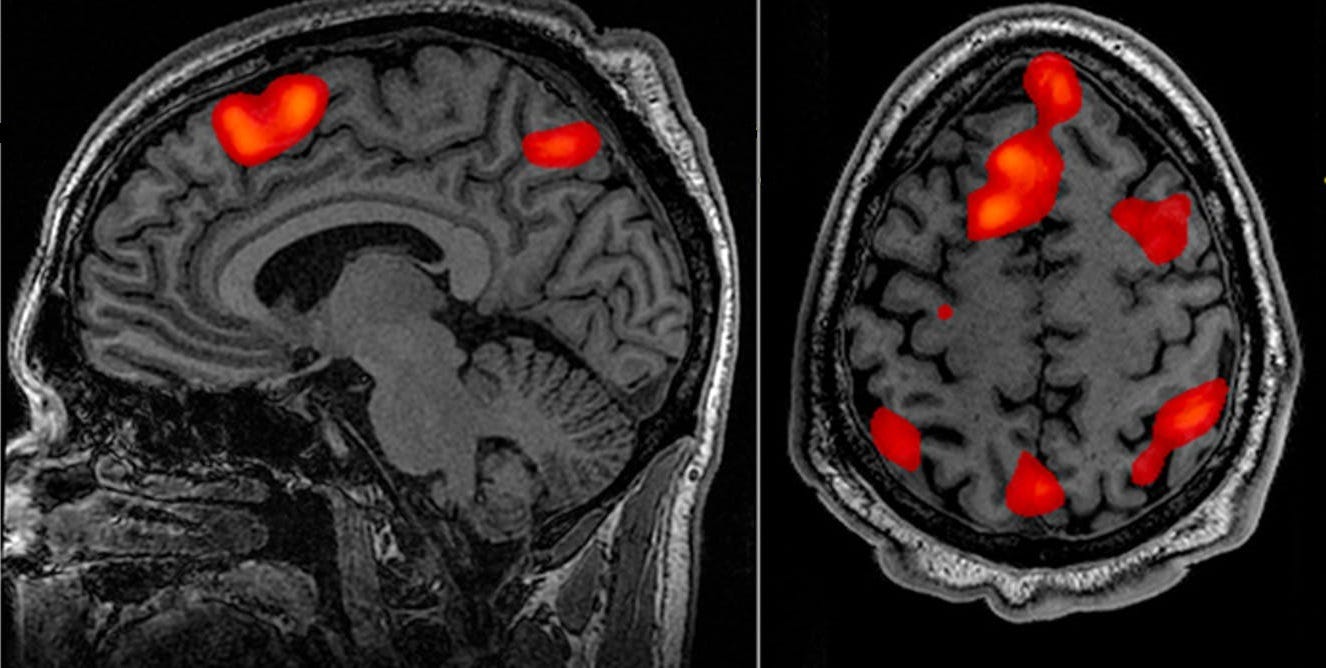

1. fMRI:

fMRI, beynimizin kan akışının ve oksijen tüketiminin yoğun olduğu yani aktif olarak daha çok çalışan bölgeleri tespit eden bir görüntüleme yöntemidir. (Türkçesi: fonksiyonel manyetik rezonans görüntüleme)

fMRI cihazları ile elde edilen veriler bilgisayar yazılımları ile görsellendirebiliyoruz. Bu sayede kişinin herhangi bir görevi yerine getirirken beyninin hangi kısımlarının daha aktif olduğunu öğrenebiliyoruz. Bu yöntem sayesinde sinir bilimi çok önemli ilerlemeler kat etmiştir.